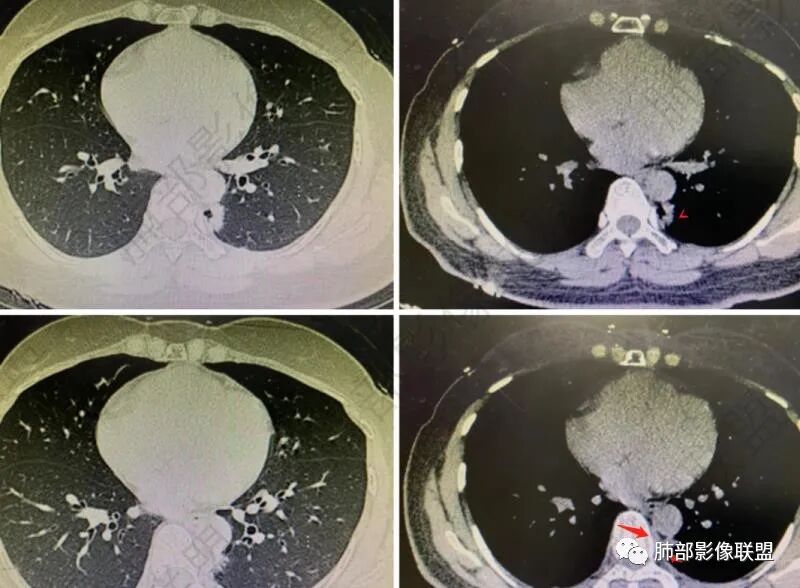

女性,体检发现,右肺上叶后段麿玻璃影!考虑AAH,左肺下叶病灶,外有毛刺伴囊腔样改变,考虑腺癌可能性大。

左肺下叶胸膜下不规则结节,边界清,短毛刺及囊腔,支气管扩张,邻近胸膜增厚,右肺上叶磨玻璃结节,边界清,考虑左肺下叶腺癌,右肺上叶AIS,鉴别炎性结节。

左肺下叶胸膜下结节,呈不规则型,边缘分叶、毛糙,内囊腔可见分隔,考虑腺癌,鉴别隔离症,右肺上叶磨玻璃结节,建议随诊。

右肺结节AIS,左肺下叶,边界似清不清,假大空,粘液腺癌要考虑。

年轻女性,左肺下叶考虑肺腺癌,右肺上叶结节,倾向AIS。一元论不排除隐球菌/其它肉芽肿性病变可能。

右肺上叶微结节边缘光滑,左肺下叶磨玻璃结节影,边界不清,左肺下叶脊柱旁斑片影,边缘未见明显磨玻璃密度影,内多个空腔影,较大者似见与支气管相通,首先考虑慢性炎症性改变,右肺上叶AIS,左肺下叶磨玻璃,炎性改变待排,抗炎后复查。

中年女性,体检发现,右肺上叶后段纯磨玻璃类圆形病灶,边缘清,左肺下叶背段纵隔旁示不规则高密度影,可见空泡影,边缘欠清。1、右肺上叶病灶考虑AAH-AIS 2、左肺下叶病灶考虑腺癌。

PGGN,小、密度低,边界清,支持原位癌。

这个需要连续的图观察,是否病灶,有待确定

囊腔应该是,周围是否有GGO?还是薄壁?

左下叶脊椎旁:囊实性

看纵隔窗:实性成分密度不高,囊张力高,内有间隔,偏胸膜侧,实性部分内部支气管聚集。

实性区域边缘平直、凹陷

首先囊的位置?为啥没考虑是空洞?空洞张力偏低一些,一般在中央一些,所以不太支持,纵隔侧几乎无壁,不太支持空洞。